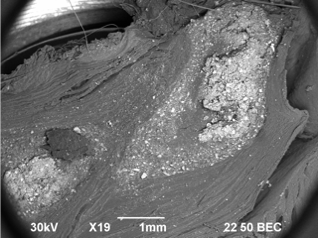

Ectopic implantation in the femoral muscle (40 mg).

Depot "allogeneic hydroxyapatite" in the muscle. first day of introduction.

Scanning electron microscopy. Magnification: 30.